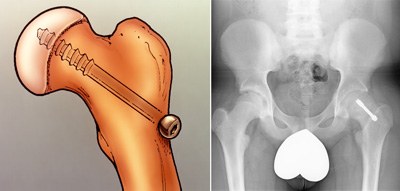

In situ fixation. This is the procedure used most often for patients with stable or mild SCFE. The doctor makes a small incision near the hip, then inserts a metal screw across the growth plate to maintain the position of the femoral head and prevent any further slippage.

Over time, the growth plate will close, or fuse. Once the growth plate is closed, no further slippage can occur.

Illustration and x-ray of in situ fixation. A single screw is inserted to prevent any further slip of the femoral head through the growth plate.

(Left) Courtesy of John Killian, MD, Birmingham, AL. (Right) Reproduced from Weber MD, Naujoks R, Smith BG: Slipped capital femoral epiphysis. Orthopaedic Knowledge Online Journal 2008; 6(2). Accessed June 2016.